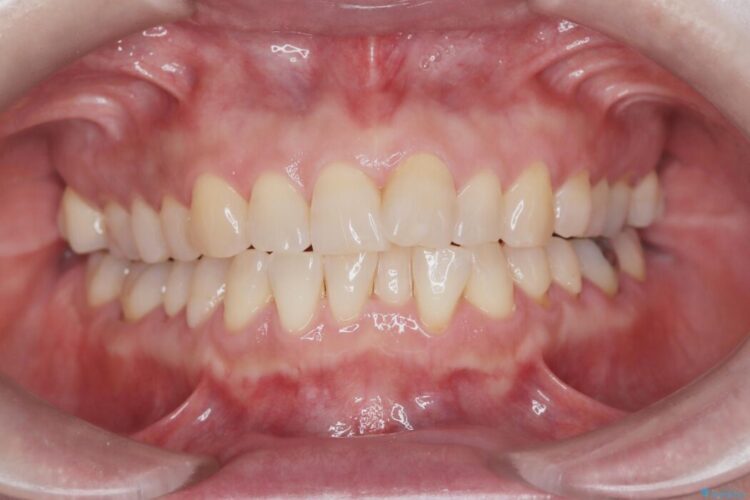

ワイヤー矯正ならではの確実な歯のコントロールにより、当初の計画通り約1年という短い期間で、前歯のガタつきが解消。見た目が美しく整っただけでなく、清掃しやすい機能的な歯並びを獲得していただけました。